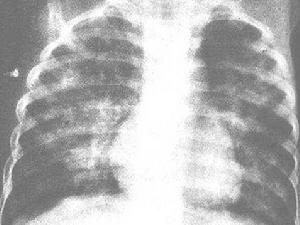

X線胸片可見雲絮狀斑片影,大小、形狀及位置都不恆定,呈遊走樣,於短期內消失及另一部位再發。偶見雙肺瀰漫顆粒狀陰影需與粟粒性肺結核鑑別。

近年來有一種"嗜酸細胞增多性哮喘病"或"暴發性哮喘性嗜酸細胞增多綜合徵",在國內若干地區暴發流行,可見於嬰幼兒、年長兒至成人。患兒不發熱或有低熱,突出表現為哮喘與乾咳,有時出現瘙癢性皮疹。病情嚴重時,偶可因支氣管、毛細支氣管梗阻及心力衰竭而危及生命。X線胸片上多數有肺紋理增加及肺氣腫,少數有片狀或網點狀陰影(圖2410)。血內嗜酸細胞增多可高達20%以上。病因未明,有些作者認為是蛔蚴在體內移行的表現,有人推測一部分流行可能與病毒感染或真菌孢子大量吸入有關。